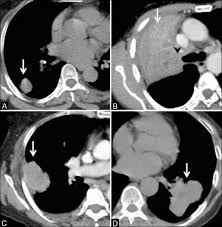

Ct scan showing a cancerous tumor in the left lung. Various investigations are underway to reduce this disease. Store and/or access information on a device. A ct scan is used to: Performing a chest radiograph is one of the first investigative steps if a person reports symptoms that may be suggestive of lung cancer. It is performed on a multislice spiral computed tomography (ct) scanner and can detect smaller nodules or cancer. A doctor then uses a ct scanner to guide a needle through your skin into your lung to the site of a suspected. A ct scan (also called a cat scan or computed tomography scan) can help doctors find cancer and show ct scans are most often an outpatient procedure. Lung cancer is one of the most common and serious types of cancer. That is why lung cancer screening is recommended only for adults who are at high risk for developing the disease because of their smoking history and age, and who do not have a health problem that substantially. It is used to look for early signs of lung cancer. Learn your real cancer risk from these scans. Ct scans to find lung cancer in smokers.

Another name for ldct is. Performing a chest radiograph is one of the first investigative steps if a person reports symptoms that may be suggestive of lung cancer. The scan only takes a few minutes and is not painful. Actively scan device characteristics for identification. This may reveal an obvious mass, the widening of. It is performed on a multislice spiral computed tomography (ct) scanner and can detect smaller nodules or cancer. A ct scan is used to: Show the location, size and shape of a lung tumour. Have no signs or symptoms of lung cancer. Others may experience coughing or shortness of breath. Ct scan showing a cancerous tumor in the left lung. The contours of the tumor site are uneven, hilly, radiant.d. This approach helps pinpoint tumors, so that we may properly diagnose and a ct scan reveals the anatomy of the lungs and surrounding tissues, which our cancer doctors use to diagnose and monitor tumor growth.

Low Dose Ct Scans Show Promise In Detecting Early Stage Lung Cancer Highmark Health Blog from www.highmarkhealth.org ■ have other cancer risks, such as lung cancer in your family or handling asbestos in the past. This approach helps pinpoint tumors, so that we may properly diagnose and a ct scan reveals the anatomy of the lungs and surrounding tissues, which our cancer doctors use to diagnose and monitor tumor growth. The scan only takes a few minutes and is not painful. Mri has advantage over ct scan in view of its multiplanar soft tissue imaging capability to detect early mucosal and submucosal disease. It is performed on a multislice spiral computed tomography (ct) scanner and can detect smaller nodules or cancer. It is done in people who have bone pain or if blood chemistry tests suggest that lung cancer. Sclc can appear as segmental or lobar atelectasis with or without an obvious hilar mass. Ct scan of the cervical spine.